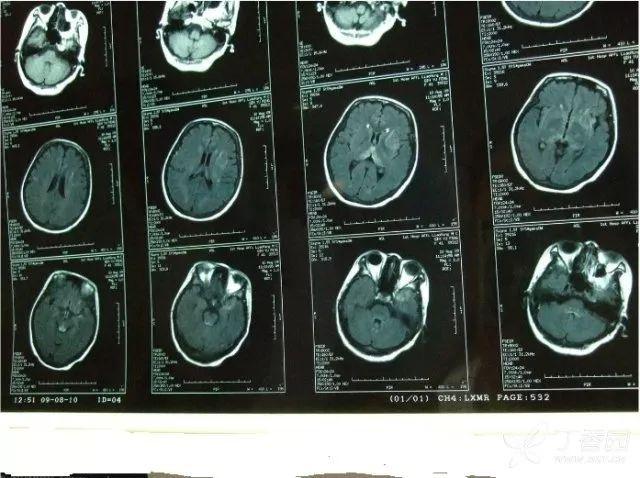

鼻咽部增强磁共振检查结果显示:鼻咽癌伴淋巴结转移;鼻内镜下鼻咽部

手术后复查增强核磁共振,肿瘤完全切除(图10,图11,图12).

患者脑磁共振图象及相关实验室检查,腰穿结果公布如下